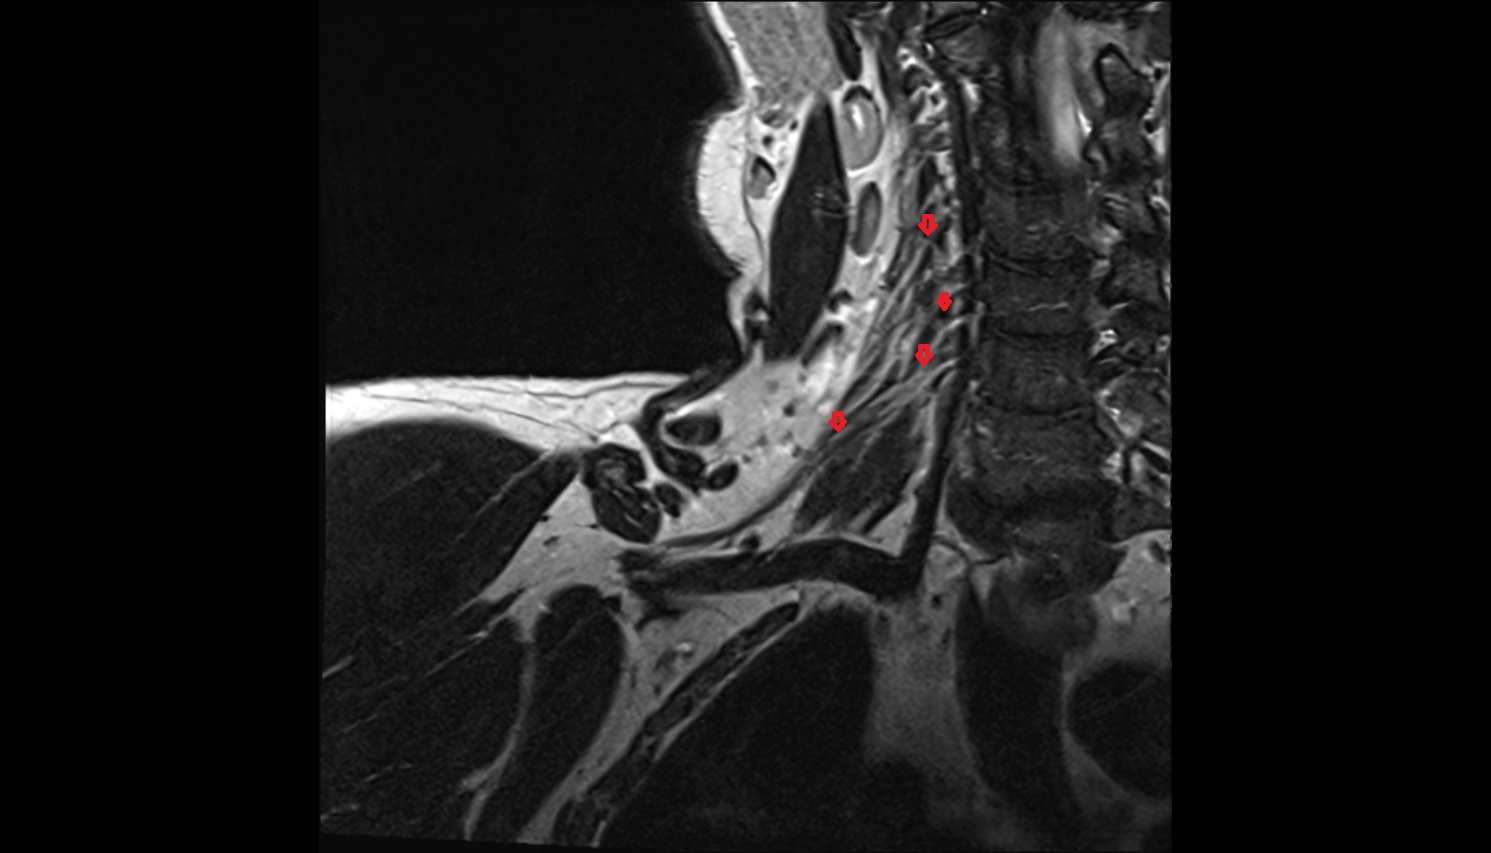

- Spinal cord

- Upper cervical spinal cord

- subarachnoid space of spinal cord